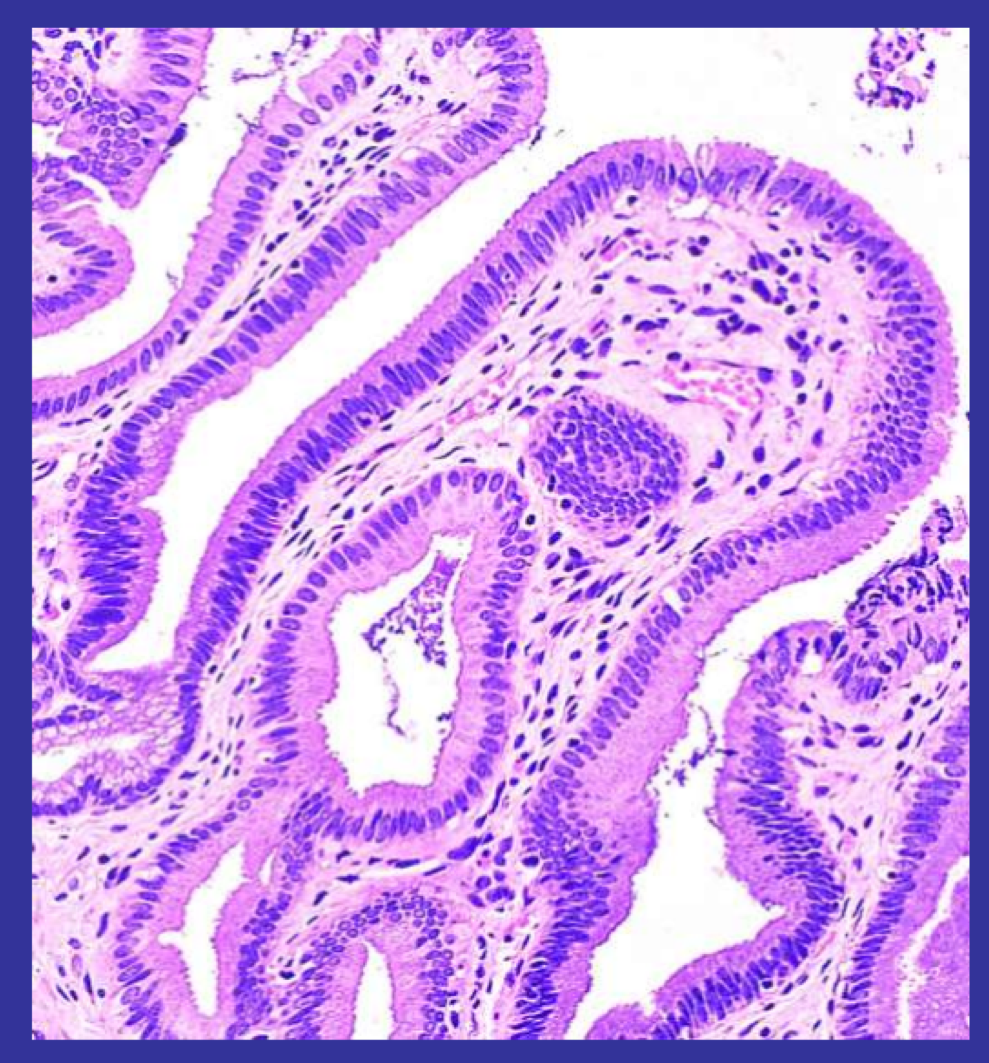

A - Longitudinal muscle layer

B - Circular muscle layer

C - Submucosa - loose connective tissue under a mucous membrane

D - Region of epithelium and subtending lamina propria (loose connective tissue)

E - Intestinal villi - increase the jejunal surface area. An examination of the edge of a villus at high power reveals the simple columar epithelium